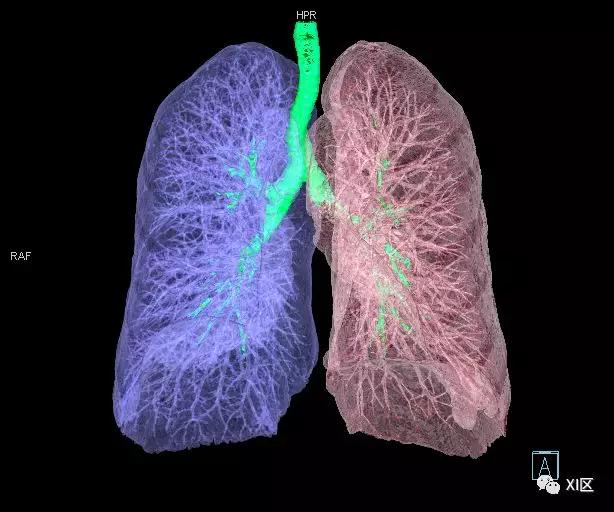

前后位,双侧位,后前位显示气道肺与胸部骨骼的关系

气管支气管树与两肺融合显示

气管支气管形如树状,因此也称气管支气管树。

气管树与左右肺的关系

气管树与胸部其他结构的关系